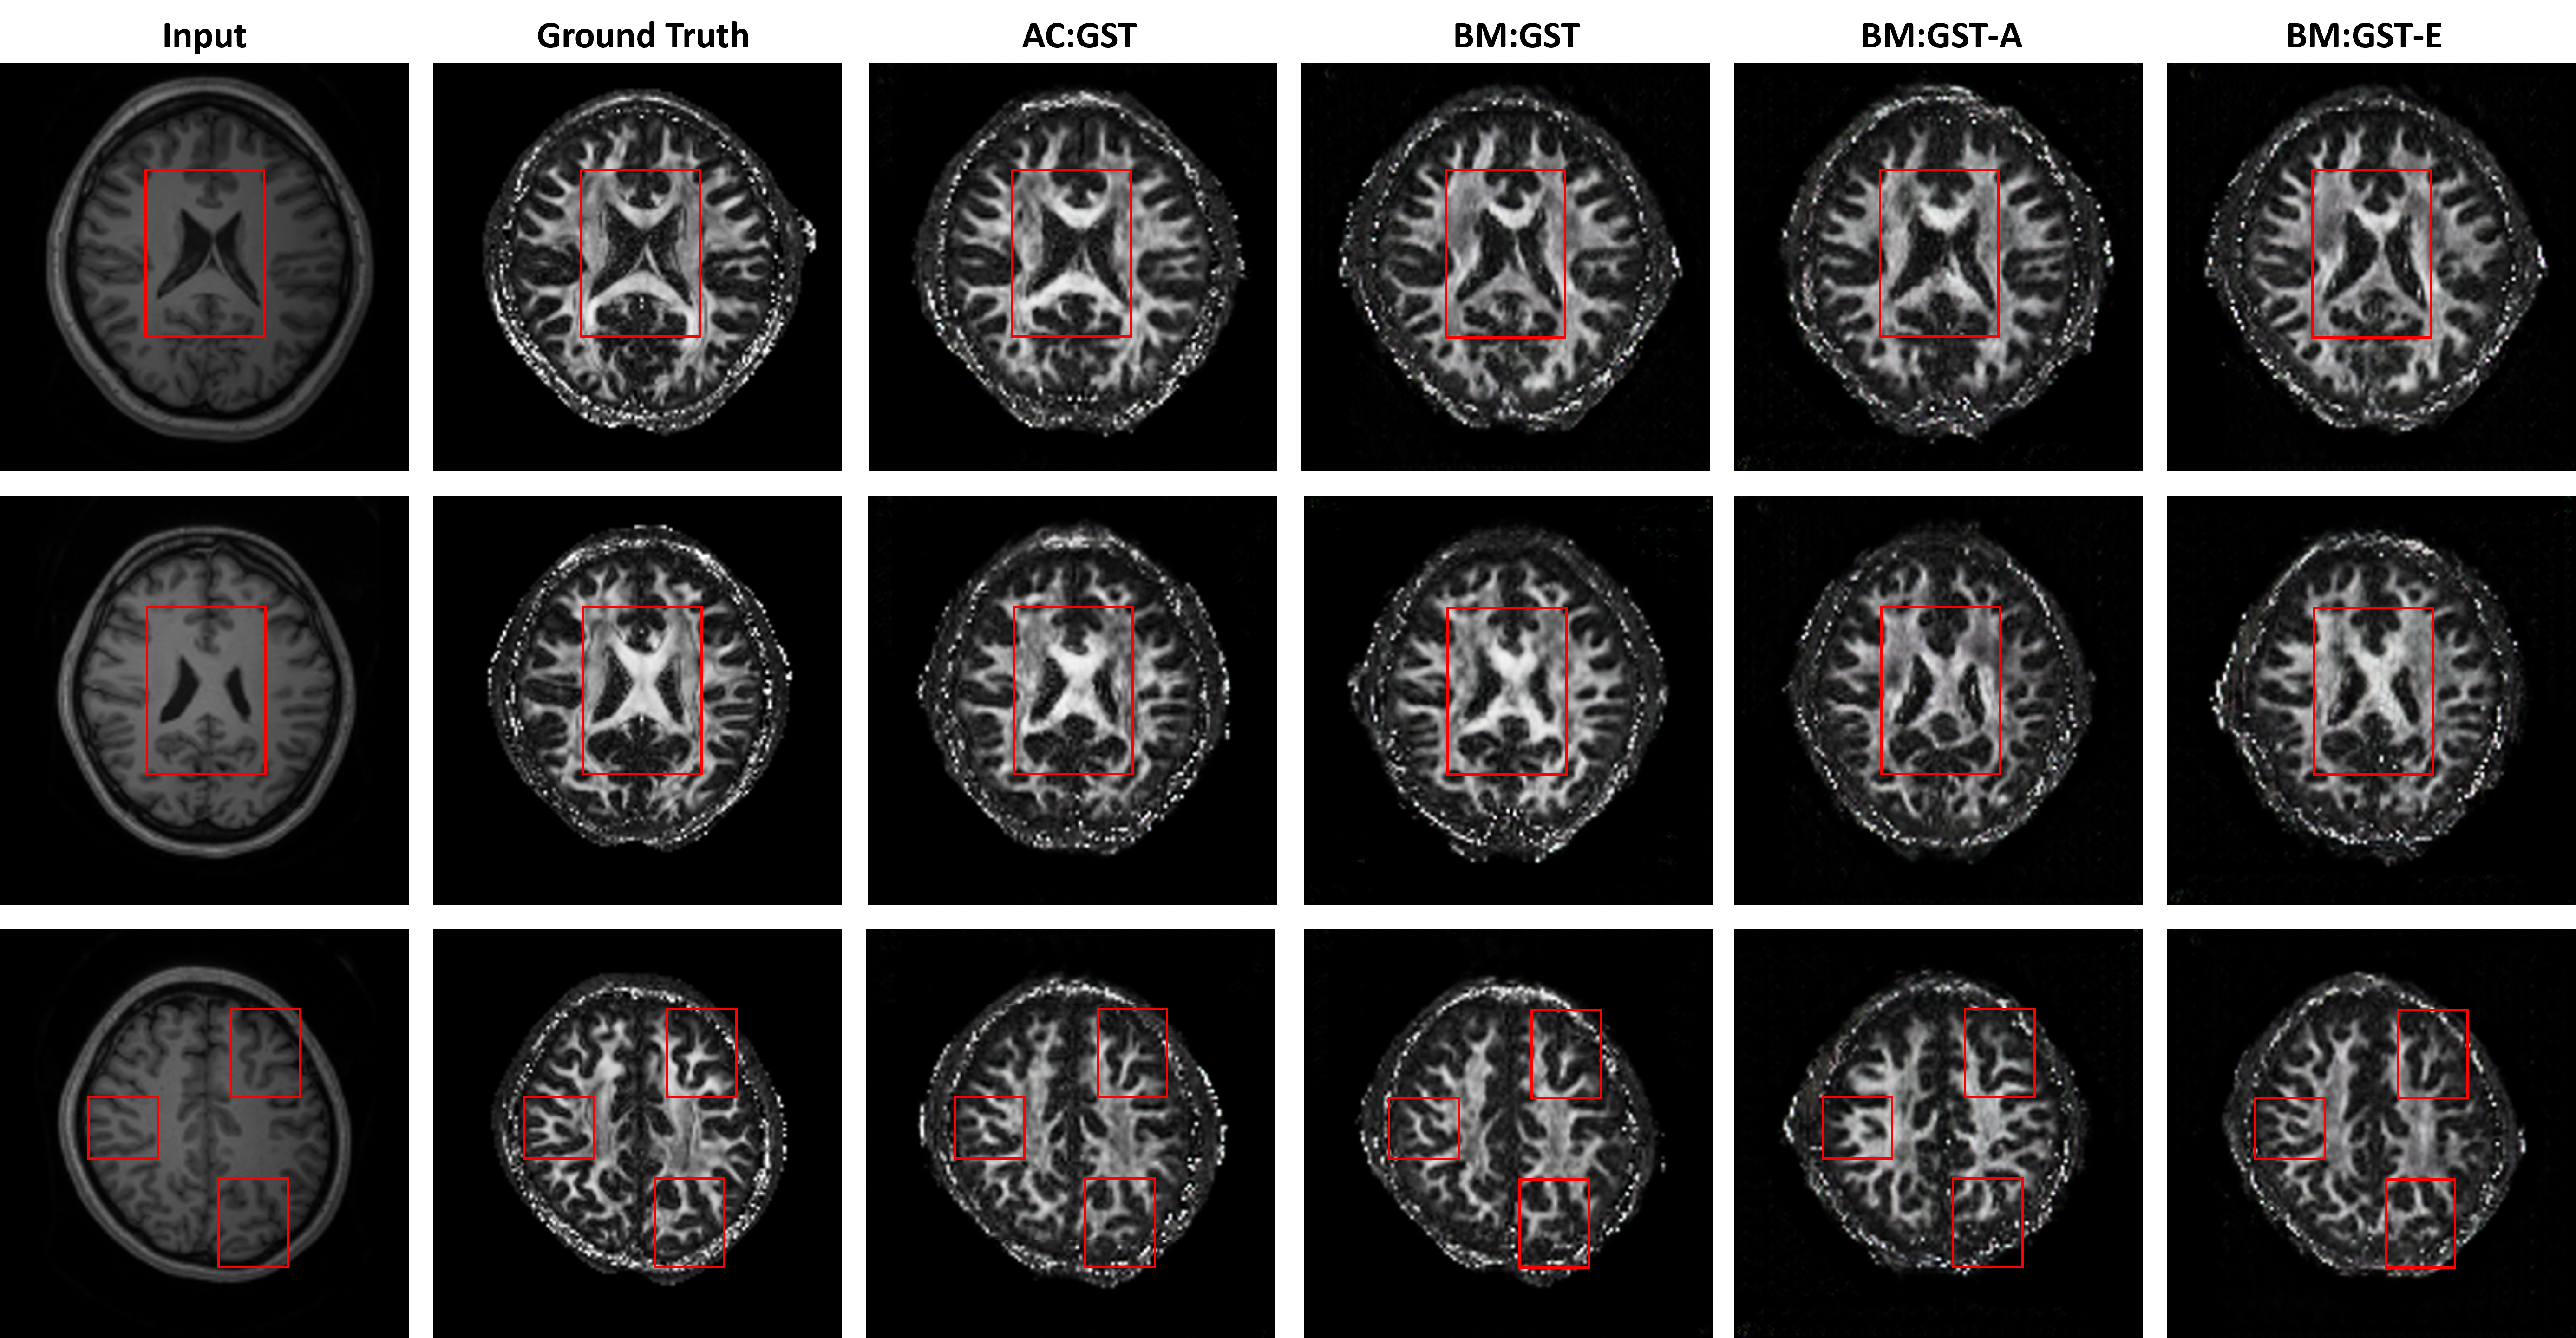

Refer to caption

Fig. 5: Ablation studies of our proposed AC:GST, BM:GST, BM:GST-A, and BM:GST-E for within UMB cross-scanner tagged-to-cine tongue MR image translation. The red rectangle indicates the tongue region used for tongue motion analysis.

We denote our proposed framework as AC:GST, which uses the self-attention continuous reliability mask, and BM:GST, which uses the binary reliability mask as in [34]. For our ablation studies, we evaluated AC:GST without the attention scheme (denoted as AC:GST-𝒜𝜽subscript𝒜𝜽\mathcal{A}_{\bm{\theta}}) and without the continuous reliability mask (denoted as AC:GST-C). Additionally, we carried out experiments, where the epistemic or aleatoric uncertainty is ignored in our uncertainty quantification, which are denoted as -E or -A, respectively. We report the results as mean±plus-or-minus\pmSD over three evaluations.

In the ablation study, the results in Fig. 5 demonstrate that AC:GST with the self-attention continuous reliability mask outperforms AC:GST-𝒜𝜽subscript𝒜𝜽\mathcal{A}_{\bm{\theta}}, AC:GST-C, and BM:GST. Additionally, the comparison between BM:GST-E, BM:GST-A, and BM:GST demonstrates the advantage of considering both aleatoric and epistemic uncertainties for the mask.